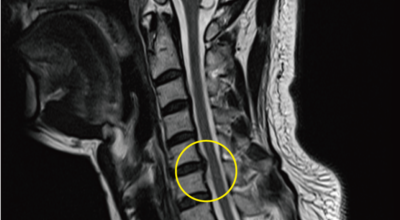

경추 사이의 추간판(디스크)이 탈출 또는 파열되어 경추신경이 자극이나 압박을 받아 통증이 생기는 증상을 말해요. 경추는 운동성이 큰 부위로 추간판이 압력을 받으면 튀어나와 척수나 신경을 압박하게 되는데요 목디스크는 퇴행성 변화 이후에 발생되기 때문에 많은 환자들이 만성적인 통증을 지니고 있는 경우가 많아요. 급성으로 생기는 경우는 교통사고, 추락, 스포츠 활동에 의한 목 부상으로 나타나기도 해요. 20대부터 가벼운 초기 증상으로 시작하여 옳지 않은 습관으로 악화되거나 호전되기를 반복해요. 나이가 들면 퇴행성 변화로 40~50대에 가장 많은 환자 수를 보인다고 합니다

목디스크는 본래의 자리에서 튀어나온 디스크의 일부 및 척추 뼈에서 생긴 골극이 양쪽 어깨, 팔, 손으로 가는 신경을 눌러 발생되는 질병입니다. 따라서 신경이 목 부위에서 훼손을 입으면 팔과 손으로 통증이 뻗어나가는 방사통이 생겨나게 되어요.

비수술적 치료가 효과가 없다거나 디스크의 신경압박이 정도가 심한 경우엔 시술할 관조차 들어갈 공간이 없으니 비수술을 고집하는 경우 주변의 정상조직까지 훼손이 될 위험이 있답니다. 미세 현미경 수술이나 인공 디스크 치환술 및 경추유합술을 통해서 치료가 가능한데 가급적 비수술치료가 권장되지만 정확한 진단이 먼저되어야 하기 때문에 자세한 사항은 전문의와 상담해서 결정하는 것이 좋을겁니다.